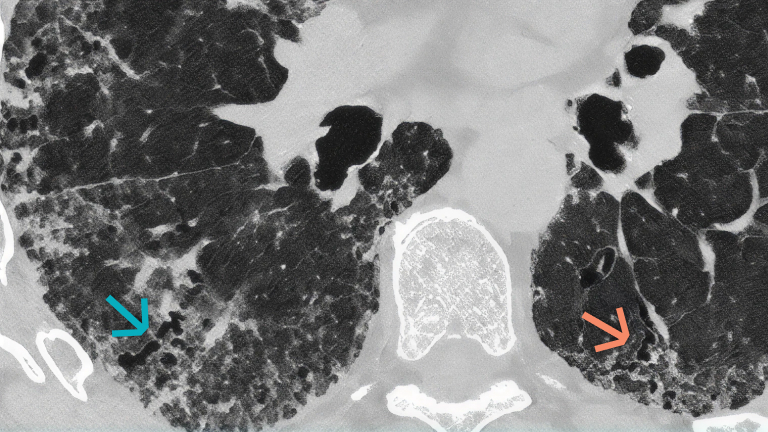

The pathogenesis of fibrotic interstitial lung disease in connective tissue diseases involves a complex interplay of inflammatory and fibrotic processes. Patients with connective tissue diseases (CTDs), such as rheumatoid arthritis, systemic sclerosis and primary Sjogren’s syndrome, develop fibrotic interstitial lung disease (ILD) via common pathogenic processes, irrespective of the underlying diagnosis or trigger. Fibrotic ILD often develops early in the course of a CTD. For example, in a study of systemic sclerosis patients, approximately 24% of systemic sclerosis-associated ILD patients showed an extent of more than 10% pulmonary fibrosis on high-resolution computed tomography at their baseline systemic sclerosis diagnosis. At the cellular level, ILD in CTDs is triggered by repeated tissue injury which induces an inflammatory response, and releases probiotic mediators, including VEGF, PDGF and FGF. These contribute to the recruitment and activation of leukocytes and fibroblasts. Resulting in a complex interplay of inflammatory and fibrotic processes. Activation of leukocytes also produces profibrotic mediators leading to further activation of the fibrotic process with excessive secretion of extracellular matrix. Excess extracellular matrix increases lung tissue stiffness, further activating fibroblasts in a feed-forward loop of self-sustaining progressive pulmonary fibrosis. Pulmonary fibrosis causes irreversible destruction and architectural disruption of the lung tissue. Based on the pathogenesis of fibrotic interstitial lung disease in connective tissue diseases, a new treatment paradigm of CTD-ILDs suggests to not only target inflammation but also fibrosis.